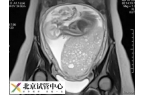

在试管婴儿移植后,如果患者出现了葡萄...